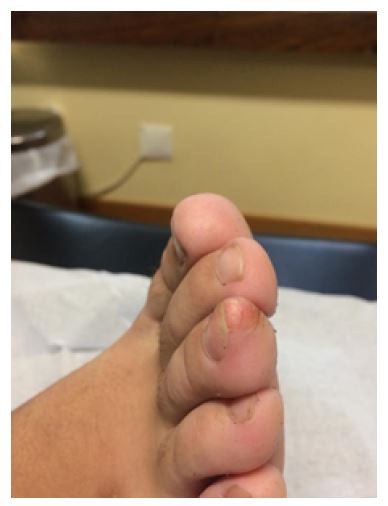

An otherwise healthy 10-year-old boy presented with a 2-year history of a painful nodule on the third finger of the right foot (Figure 1). There was no history of trauma. He had undergone multiple wart and antifungal treatments without improvement. Physical examination revealed a firm nodular lesion under the nail plate measuring 1 cm in diameter with regular borders and nail deformity. No similar nodules were found elsewhere. Right foot radiograph showed a bony prominence arising from the terminal end of the distal phalanx (Figure 2).

The patient was diagnosed with SE and referred to orthopedic consultation. Excision of the nodule was performed without intercurrences. Anatomopathology confirmed the diagnosis of SE.

SE is a painful benign osteochondral proliferation of the distal phalanx of the fingers or toes, most commonly affecting the hallux.1-5 Progressive growth of the lesion may cause nail lifting and deformity.4 The etiology of SE is unknown, although trauma and chronic infection seem to play a role.3,5 Half of the cases occur in patients under the age of 18 years, and females are predominantly affected.2,5 The differential diagnosis is broad and should include other subungual masses such as osteochondroma, pyogenic granuloma, keratoacanthoma, wart, or fibroma.4 Radiograph of the affected digit is essential for diagnosis and shows a dorsal or dorsomedial surface proliferation of the distal phalanx.1,5 Histopathology typically shows endochondral ossification with lamellar trabeculae covered by a fibrocartilaginous cap.1,4 As this is usually a progressive condition, treatment consists of complete marginal surgical excision.1-5 Postoperative nail deformity may persist, and recurrence has been reported.1,2

Although SE is not a rare entity, a diagnostic delay of 12 months is common,2 highlighting the importance of a high index of suspicion for this entity by all physicians working with children, as it can affect their quality of life.3